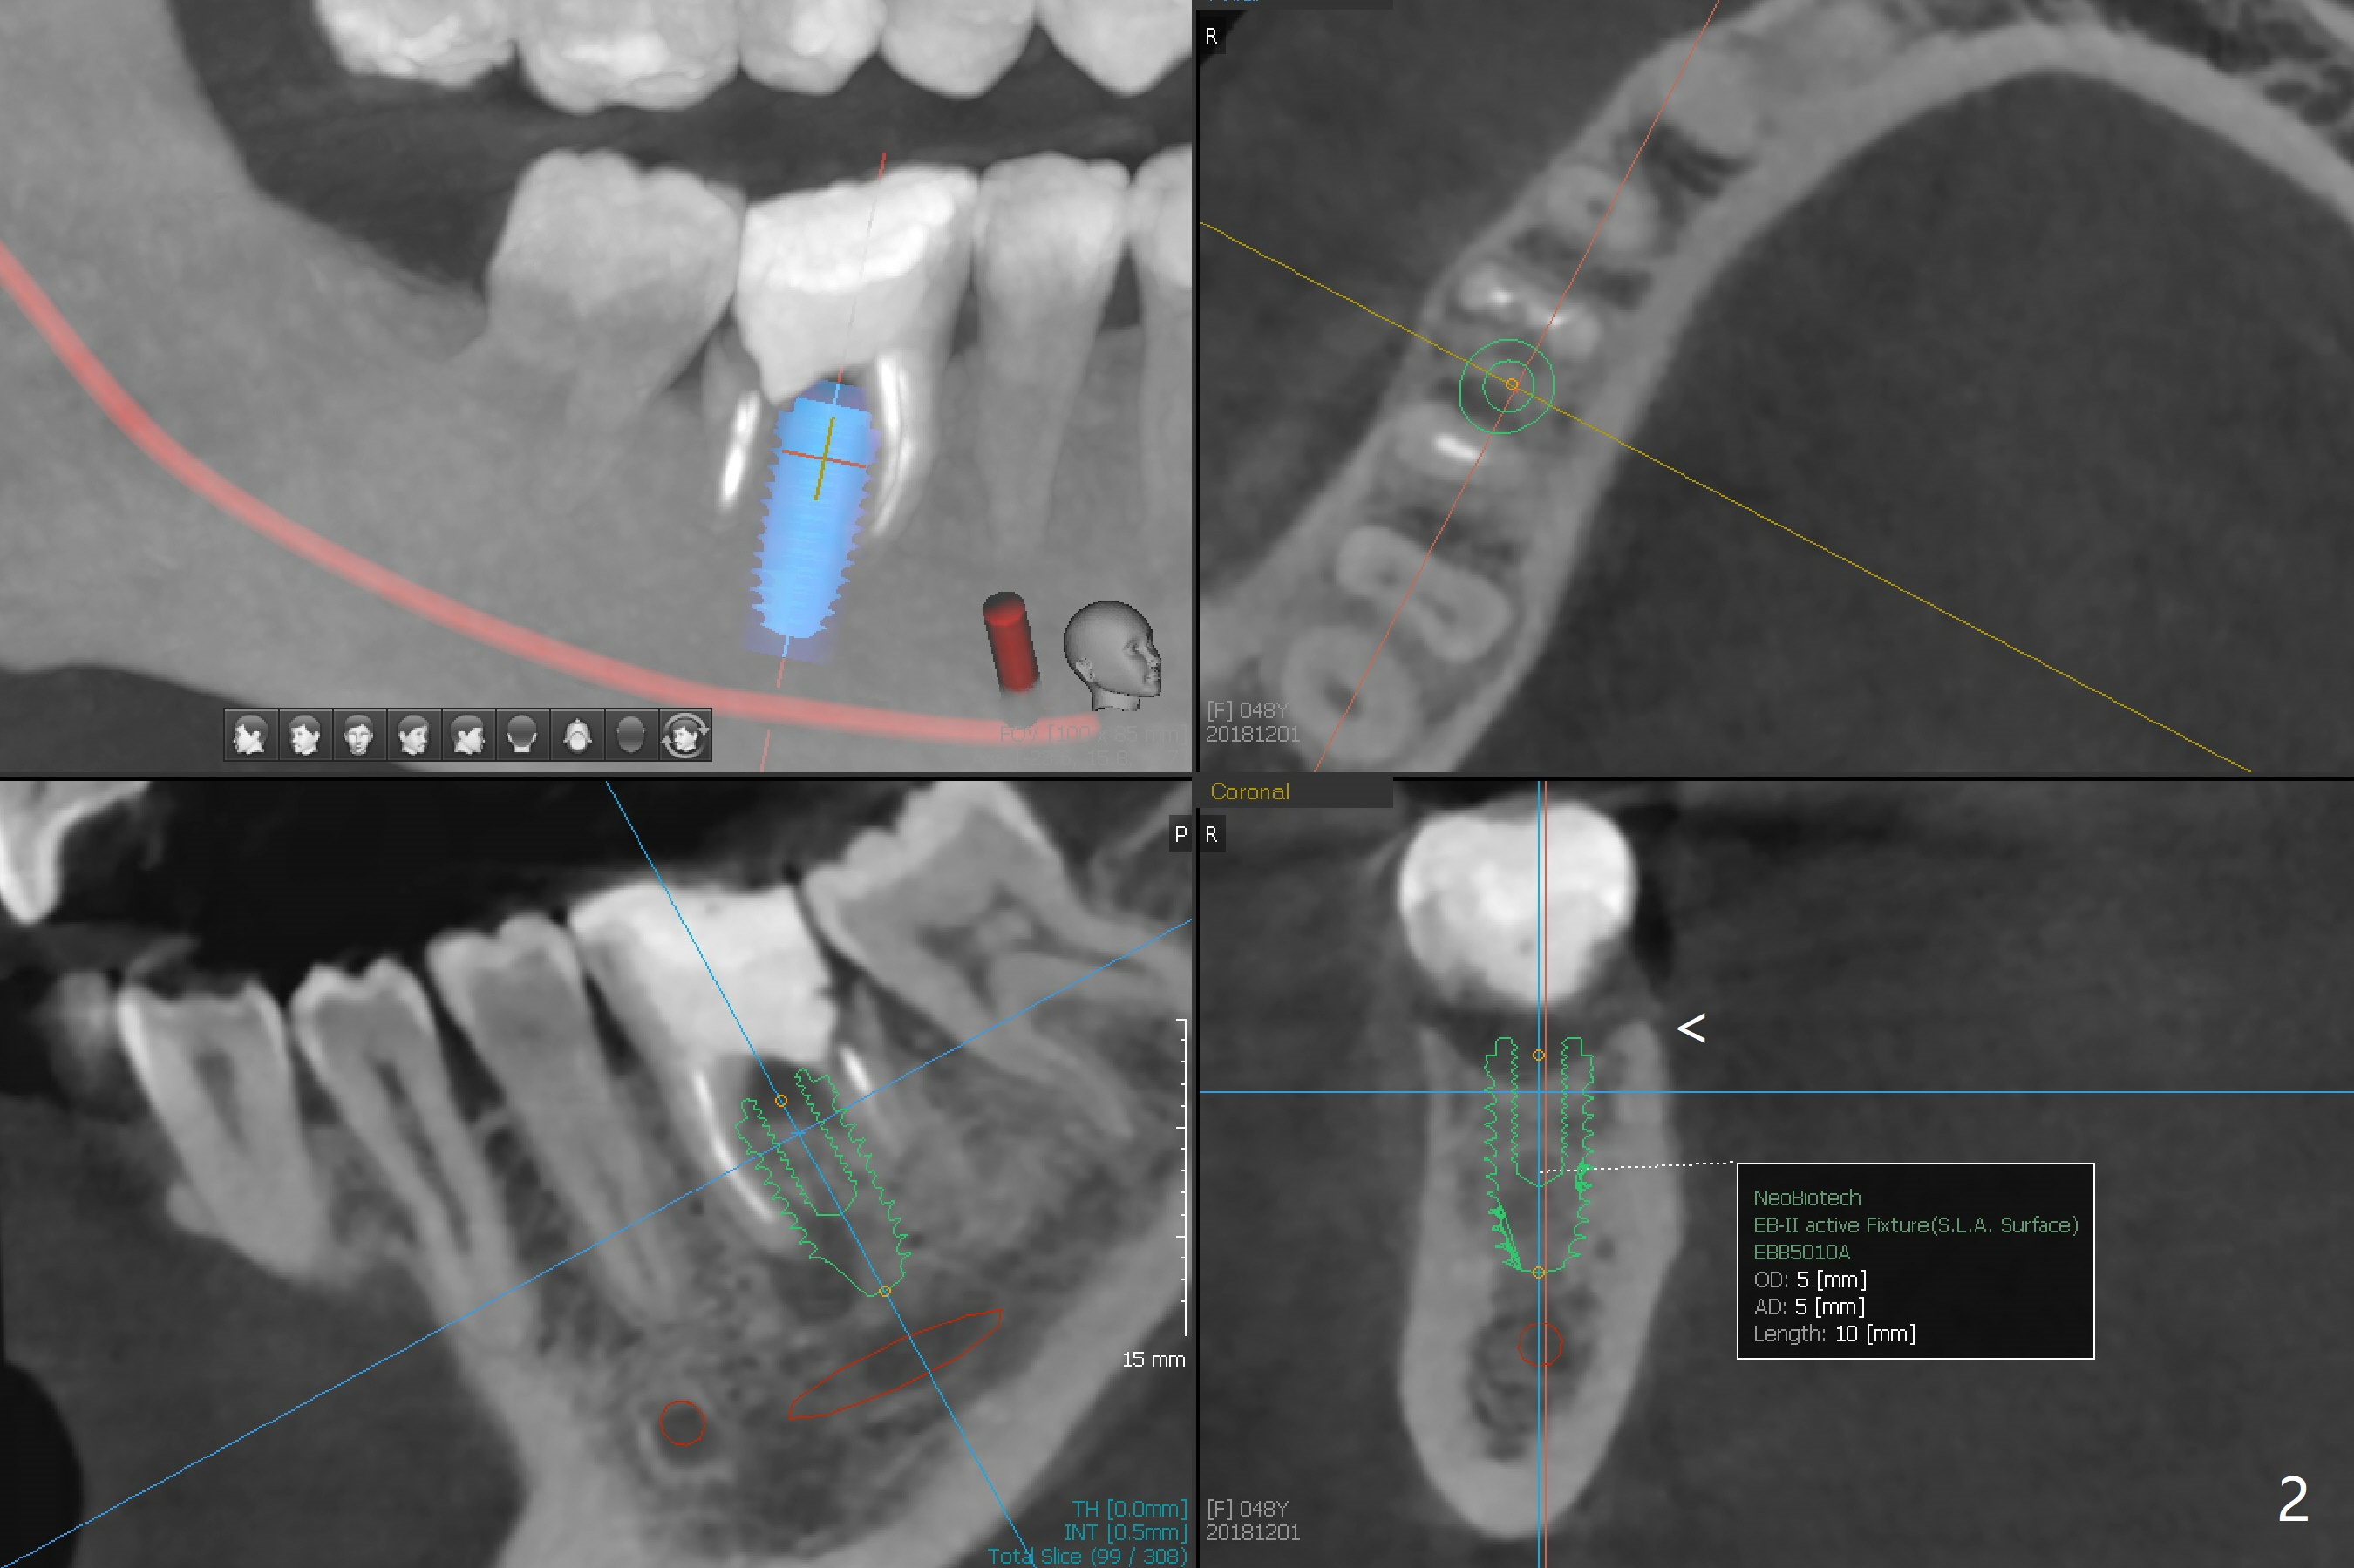

A 48-year-old woman has chewing pain at #30 with distal root fracture and a large mesial apical lesion (Fig.1). To reduce abutment screw loosening, guided surgery is planned with implant placed at the crestal level (Fig.2 <). Because of the large apical lesion, a longer implant (11.5 mm) will be placed than that Fig.2 indicates.